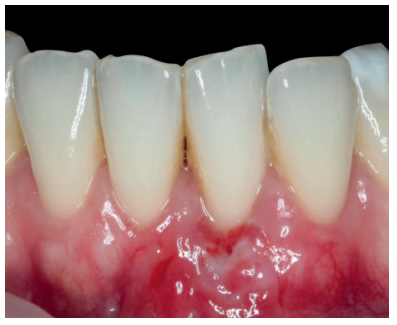

Se realizó control a la semana de la intervención (Figura 4) y tras 15 días se retiró la sutura, observando la revascularización del injerto y la epitelización del área cruenta apical al sobre (Figura 5). Se realizó seguimiento al mes (Figura 6), a los 3 meses (Figura 7) y al año y medio del procedimiento (Figura 8).